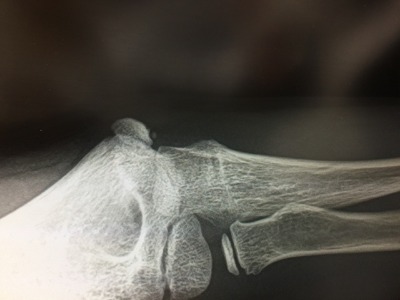

9歳男の子 内側型 上顆裂離骨折について

内側上顆の裂離骨折についてです。

九歳子供が、ひじの裂離骨折と診断されました。ここ二週間くらい、野球すると痛い、というので、病院につれていってレントゲンをとったところ剥離骨折との診断。

医者によると、レントゲンをみて、ずいぶん前の骨折のようなかんじだ、と。

野球肘です。